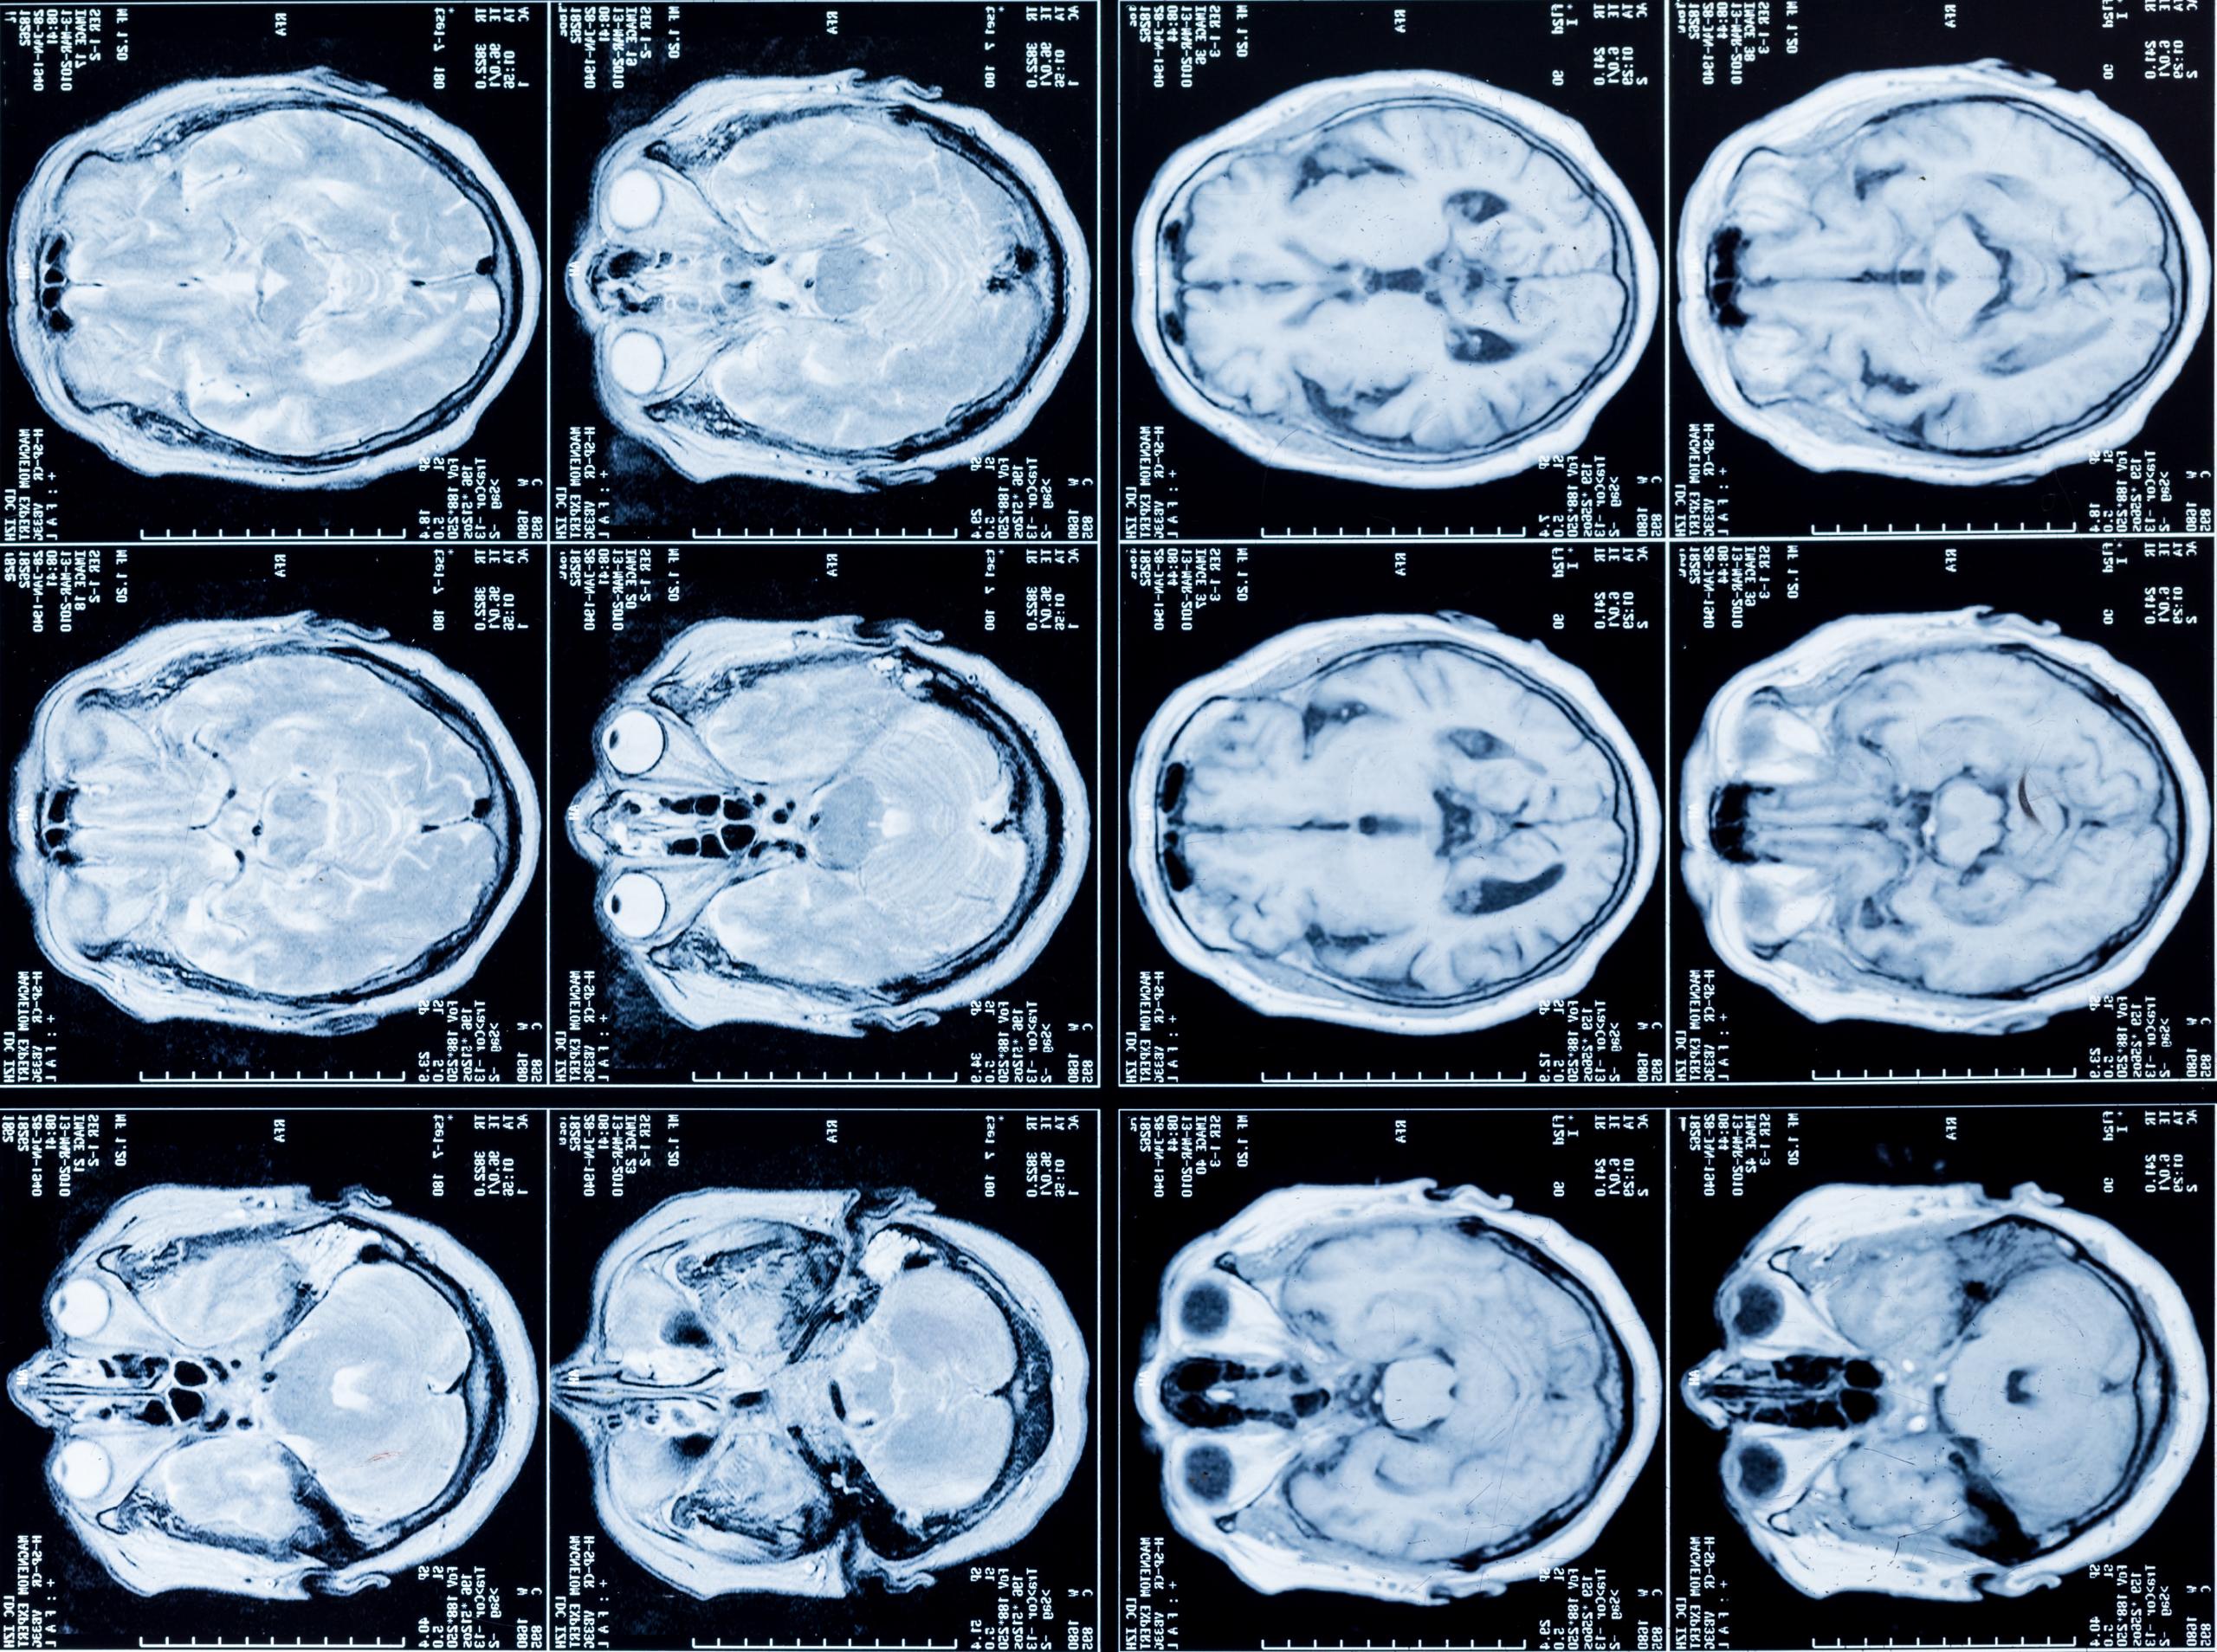

At Viva Medical Center in Doral, Florida, we provide expert neurology and neurosurgery services to diagnose and treat complex conditions affecting the brain, spine, and nervous system. Our goal is to improve each patient’s quality of life with personalized care, advanced diagnostics, and cutting-edge treatment options.

Our team of experienced neurologists delivers precise diagnosis and effective management for a wide range of neurological conditions. Using modern imaging and neurophysiological tools, we ensure a thorough and accurate evaluation.

• MRI, CT scans, and EEG test readings for diagnostics